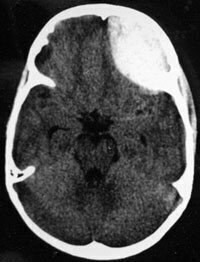

L’examen clinique montre effectivement des mouvements intermittents, brusques de l’hémicorps droit que le sujet tente de camoufler par des mouvements volontaires. Le reste de l’examen neurologique et de l’examen clinique général est normal, notamment l’examen ophtalmologique.

Mouvement arythmique, brusque, imprévisible et souvent de rotation, touchant des territoires variés, survenant sur un fond d’hypotonie.